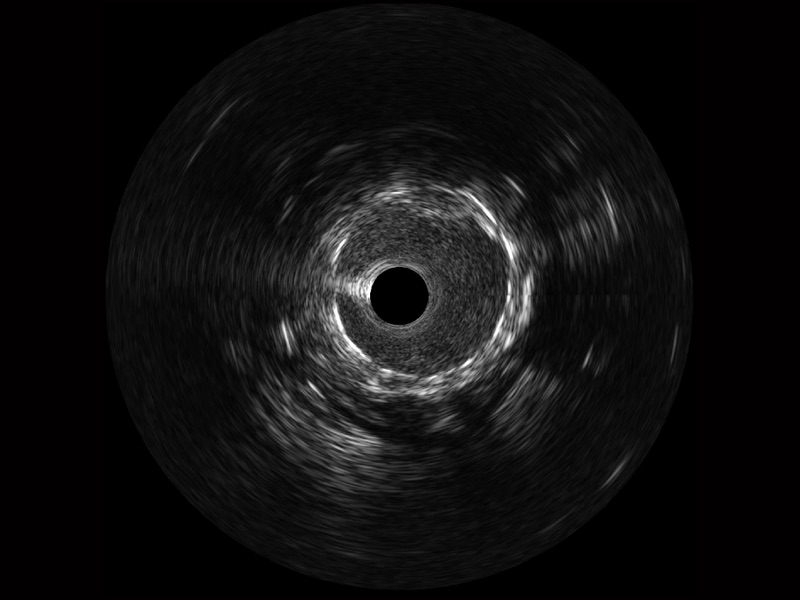

• 传统IVUS图像

对比传统IVUS导管成像,乐玩lewin国际宽频IVUS图像的近场支架梁显影更细腻,远场中膜外血管仍清晰可辨,兼顾远中近,兼顾分辨力与穿透深度